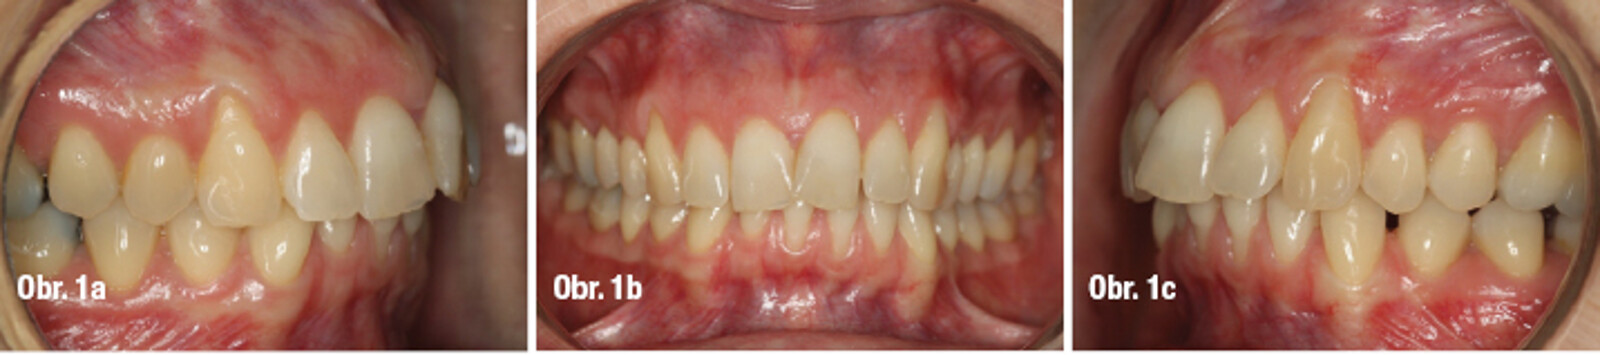

Lingvální zámky 3M™ Incognito™ System a kombinovaná ortodontickochirurgická terapie